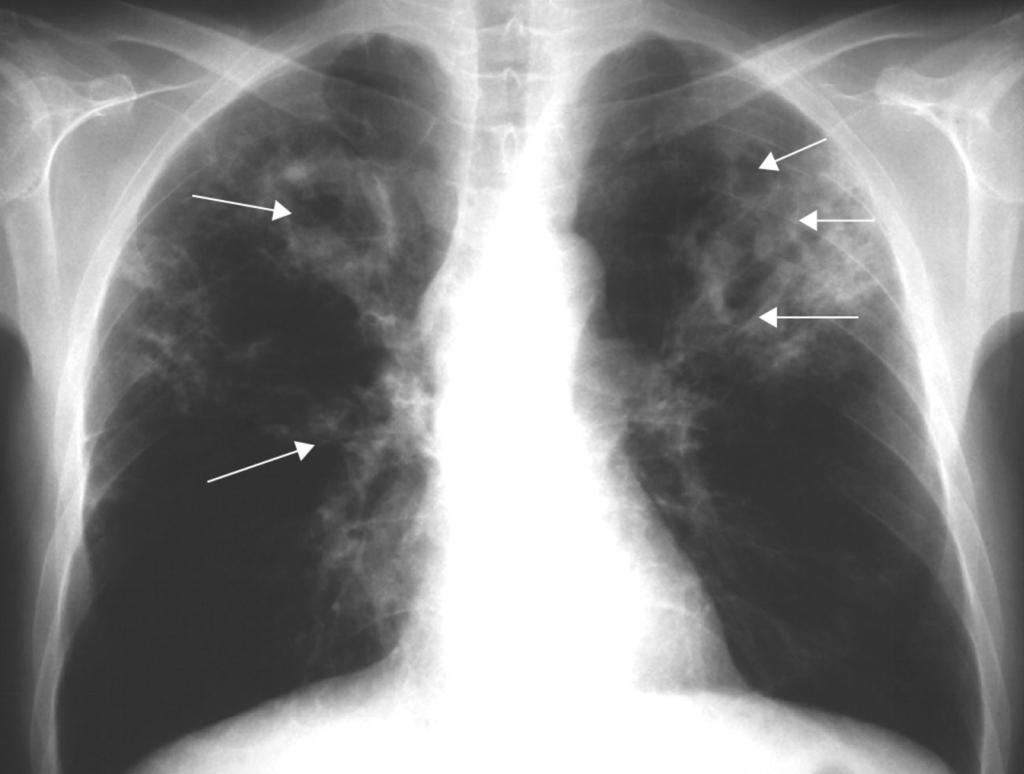

Диссеминированная форма

Эту форму туберкулеза можно поделить на острую, подострую и хроническую. Как правило, развивается остро со стремительным распространением туберкулезных палочек по всему организму.

Выделяют еще одну классификацию в зависимости от способа распространения микобактерий:

- гематогенное — на рентгене проявляется более крупным размеров очагов, находящихся в верхних отделах легких;

- лимфогенное — очаги среднего размера, размещенные преимущественно в нижних отделах;

- лимфобронхогенное — характерно одностороннее поражение в нижних отделах легкого.

То, как выглядит туберкулез на снимке, зависит как от характера его распространения, так и от остроты процесса. Наиболее характерный подтип диссеминированного туберкулеза — милиарный туберкулез. Он представляет собой острую, чаще всего гематогенную инфекцию.

Ниже перечислены основные его признаки на рентгене:

- большое количество мелких очагов, несколько миллиметров в диаметре;

- очаги равномерно распространены по всему легочному полю;

- иногда очаги сливаются;

- корни легких несколько приподняты;

- иногда объем легочной ткани становится меньше.